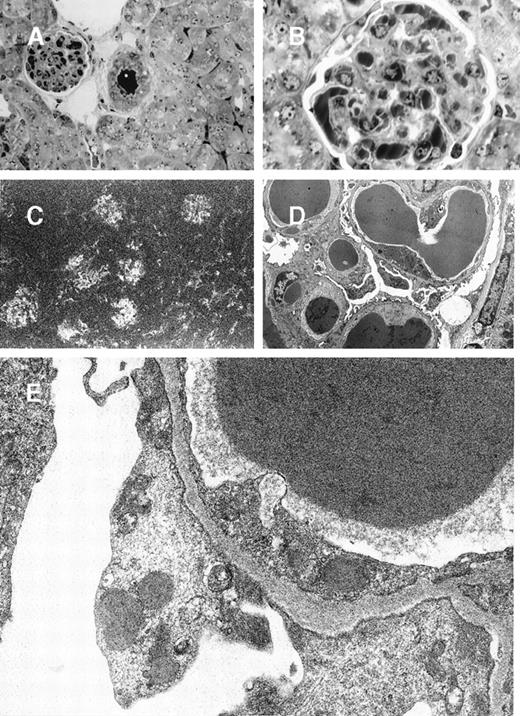

In 8A4 mice, light microscopic examination of tumor biopsies showed abundant crystal inclusions similar to Ig crystals observed in cultured cells (Figure 3). Contrasting with the absence of a monoclonal peak, kidney samples showed marked glomerular lesions with abundant wire-loop deposits along the glomerular basement membrane, predominating in mesangium on the endothelial aspect of the basement membrane and often resulting in pseudo-thrombi (Figure4A and 4B); to a lesser extent, deposits were also found on the epithelial side and occasionally invaded the urinary space. In some glomeruli, Ig deposits were associated with endocapillary proliferation and polymorphonuclear leukocyte infiltration. By immunofluorescence, deposits strongly stained with an antimouse IgG and were present within all glomeruli (Figure 4C). No deposits were found in other locations of the kidney or in liver or spleen. Electron microscopy also confirmed the crystalline nature of extracellular renal deposits by demonstrating their regular striation of 12- to 14-nm periodicity (Figure 4D and 4E). The crystals observed in vitro in cultured cells (Figure 1) and in vivo in tumoral cells (Figure 3), either by immunofluorescence staining or by electron microscopy, were identical to those formed in animals as kidney deposits (Figure 4).

Glomerular lesions in 8A4 mice kidneys.

(A and B) Light microscopy showing the proliferative and exudative changes (A, original magnification ×200, light green trichromic staining) and the voluminous depositions of material predominantly in mesangial and subendothelial areas (B, original magnification ×1000, semi-thin section, toluidine blue staining). (C) Immunofluorescence microscopy with antimouse Ig conjugate (original magnification ×200) showed intense staining of deposits strictly limited to glomeruli without any staining of peritubular capillary lumen. (D and E) Electron microscopy showed osmiophilic deposits in mesangial and subendothelial spaces (wire-loop lesion) with few subendothelial deposits. The glomerular capillary lumens were free of deposits (D, original magnification ×5000). Note the highly organized crystalline glomerular deposits formed by densely packed microtubules (external diameter = 12 nm) in transversal section and parallel arrays in longitudinal section with a 12-nm striation periodicity (E, original magnification ×60 000).